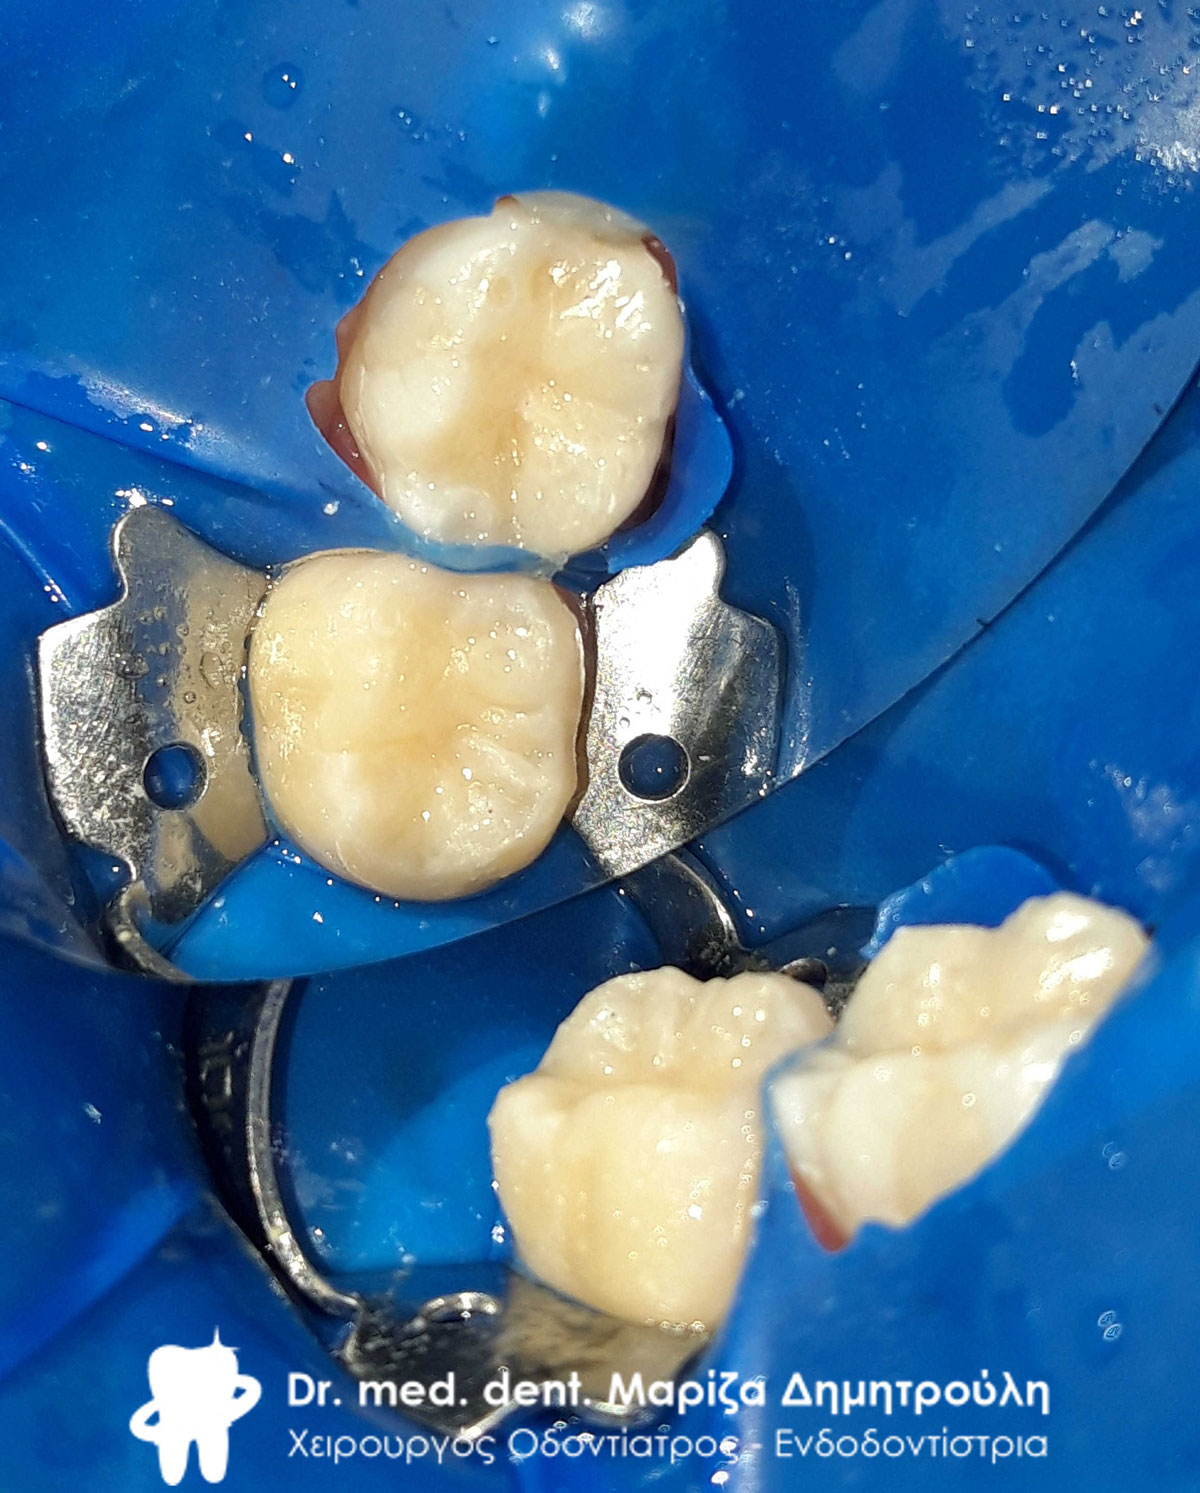

Εξαγωγή του σαπισμένου δοντιού